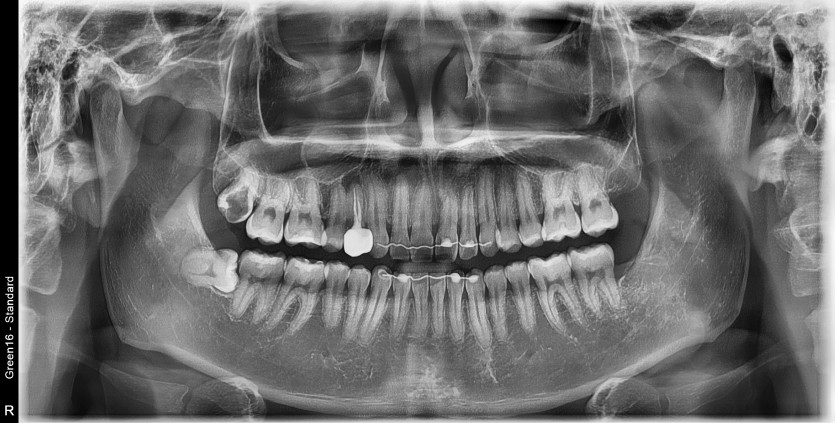

#18,48 사랑니 발치

구강 외과 전문의가 당일 발치했습니다.